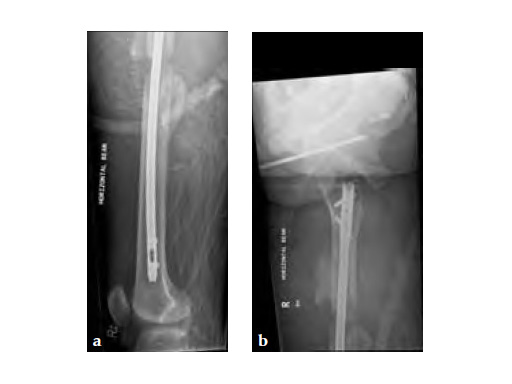

Three weeks prior to her last admission, she complains of recurrent right thigh pain for which epidural analgesics were administered for presumed radiculopathy, however preliminary x-rays and even MRI of the thigh were also taken in view of her primary complaint regarding her right thigh. These investigations did not indicate the possibility of impending bisphosphonate related femur fracture. It is clear from the radiographs that she has an obvious anterolateral bow of her femur and a thickened lateral cortex in the lateral midshaft cortical bone, which may indicate a stress fracture (see Fig 3a-b).

No edema indicated a stress fracture (see Fig 4a-b).

Based on the negative MRI thigh and positive MRI lumbar spine of multiple levels of spinal stenosis, the patient underwent epidural analgesic injection. Patient sustained right femur midshaft periprosthetic fracture the next day after her epidural injection with no trauma.

Notice the fracture decrease the emphasis on the anterolateral bow of the femur (See Fig 5a-b).

Insertion of A2FN as patient may be suffering from a stress fracture related to long term (2.5 years) bisphosphonate use. My rationale against a plate is because bisphosphonate related fractures will heal extremely slowly. In our experience even despite bone grafting union may need up to 2 years. In that time, a plate will fail in less than a year even if the patient is only allowed very minimal weight bearing.

Note despite the increased in curvature compared to other nails in the market, there is still noticeable malreduction at the fracture site (see Fig 6a-b).